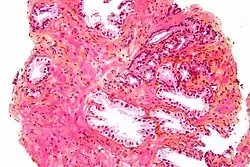

Microanatomia

A próstata consiste em tecido glandular e conjuntivo. Células altas em forma de coluna formam o revestimento (o epitélio) das glândulas.[1] Estas formam uma camada ou podem ser pseudoestratificadas.[3] O epitélio é altamente variável e áreas de células cuboidais baixas ou planas também podem estar presentes, com epitélio transicional nas regiões externas dos ductos mais longos.[9] As glândulas são formadas como muitos folículos, que drenam para os canais e, subsequentemente, para 12–20 ductos principais. Estes, por sua vez, drenam para a uretra à medida que passa pela próstata.[3] Há também uma pequena quantidade de células planas, que ficam próximas às membranas basais das glândulas e agem como células-tronco.[1]

O tecido conjuntivo da próstata é composto de tecido fibroso e músculo liso. O tecido fibroso separa a glândula em lóbulos.[1] Ele também fica entre as glândulas e é composto por feixes de músculos lisos orientados aleatoriamente que são contínuos com a bexiga.[10] Com o tempo, secreções espessadas chamadas corpora amylacea se acumulam na glândula.[1]

Glândulas microscópicas da próstata

Glândulas microscópicas da próstata